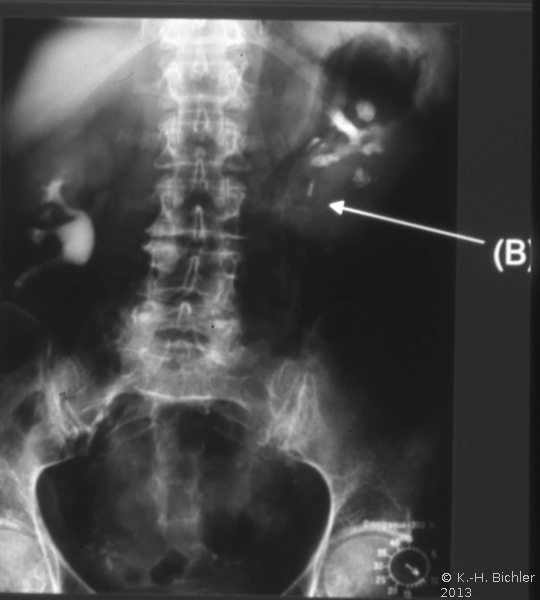

Literatur:http://www.bundesaerztekammer.de/page.asp?his=1.120.121.1042.5974; Leitlinie zur Qualitätssicherung in der Röntgendiagnostik: Qualitätskriterien röntgendiagnostischer Untersuchungen; Bundesärztekammer Stand: 23.11.2007. Sie schreibt das Verwenden von umschließenden Hodenkapseln, Ovarienabdeckungen und Bleigummiabdeckungen für den an das Nutzstrahlenfeld angrenzenden Körperbereich vor (

10 Abbildungen).